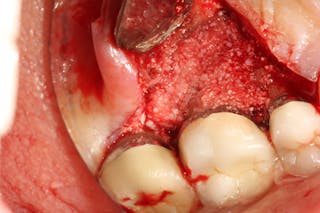

Periodontal Bone Loss Case Best Technique For Increasing Bone Height